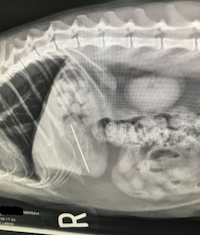

Diagnostic results: The radiographic images showed a radiopaque needle and some kibble in Mirrah’s stomach. There were no other significant findings.

As shown in the radiographic images, the needle and thread were still located in Mirrah’s stomach. Since the needle and thread hadn’t passed through the stomach yet, they could be removed using an endoscopic procedure instead of a surgical procedure. An endoscopic procedure doesn’t require an incision, so it is less invasive and has a shorter recovery period. Mirrah’s owner consented to the endoscopy.